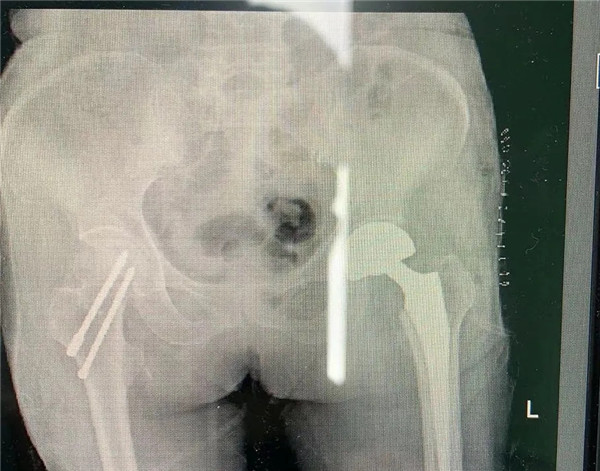

確定手術(shù)后,經(jīng)內(nèi)科、麻醉科、超聲科等專家會(huì)診后,王老太太符合手術(shù)指征,3月5日,老太太接受了股骨頭置換手術(shù)。

手術(shù)由危立軍副院長(zhǎng)主刀,用最少的時(shí)間完成人工關(guān)節(jié)置換,從劃刀到假體安裝好僅僅10分鐘。術(shù)后王老太太一天天好轉(zhuǎn)起來,現(xiàn)已下地康復(fù)行走,臉上洋溢開心的笑容。